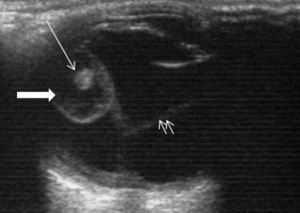

| Фото. Цистицеркоз глаз: А Киста цистицерка под конъюнктивой в наружном углу глаза; Б цистицерк на глазном дне, вертикальная стрелка указывает место выхода паразита через сосуды сетчатки поврежден пигментный эпителий сетчатки, горизонтальная стрелка указывает на отслойку сетчатки вокруг цистицерка, белое пятно в центре кисты это сколекс паразита; В На УЗИ цистицерк на глазном дне киста (толстая стрелка) и сколекс (тонкая стрелка) паразита. | ||